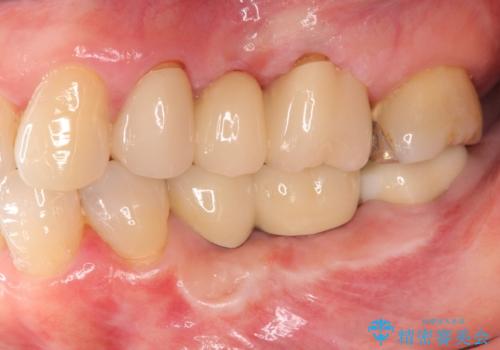

自家骨と人工骨による骨造成は、長期的に見て安定し吸収が少ないとされる骨の造成法です。

インプラント周囲に、必要十分な骨を作ることが長期渡りインプラントにトラブルを起こしにくい鍵となります。